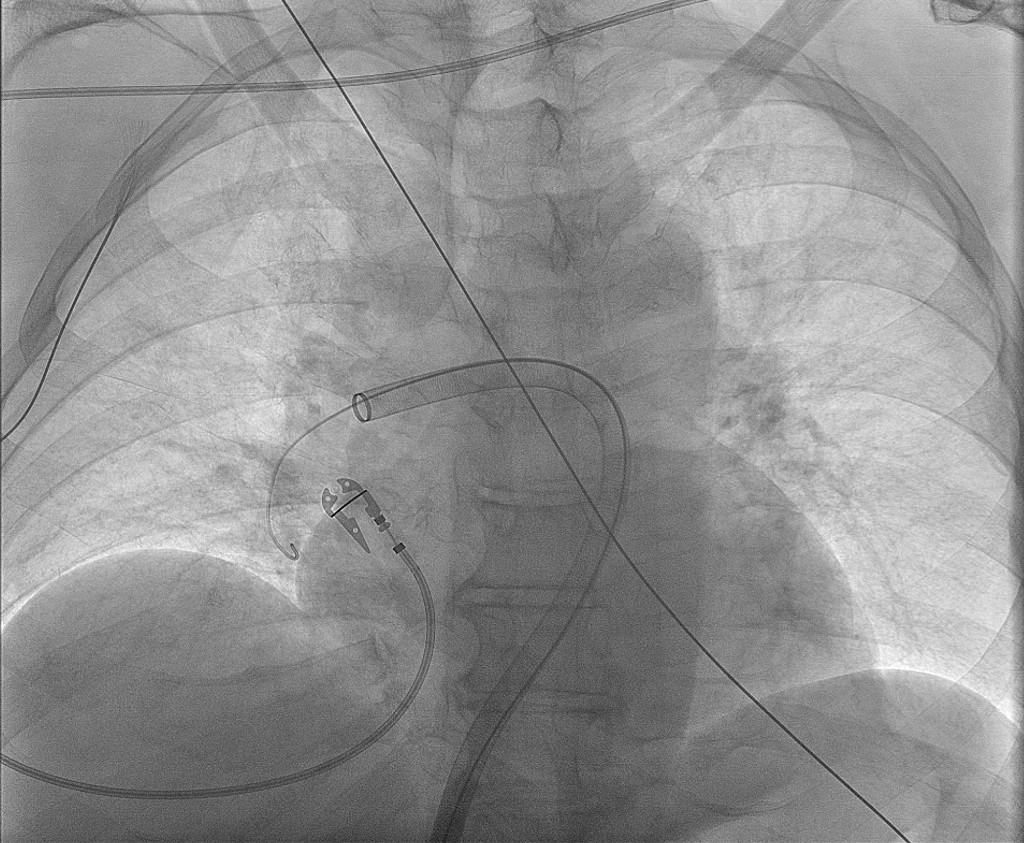

I lokalbedøvelse ble det gjort ultralydveiledet punksjon av vena femoralis communis, og et vinklet grisehalekateter ble ført via vena cava inferior gjennom høyre hjertehalvdel til arteria pulmonalis (figur 6). Middeltrykket i truncus pulmonalis ved prosedyrestart ble målt til 37–39 mmHg (< 20 mmHg). Trombektomiutstyret som ble brukt, var FlowTriever (Inari Medical). Via 24 Fr og 16 Fr katetre ble det aspirert trombemasser fra begge lungers karsenger (figur 7). Totalt ti aspirasjoner ble utført.